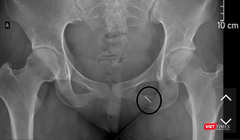

Phim X-quang thể hiện cây kim may đâm và chui sâu vào cơ thể bệnh nhân

Hy hữu: Phẫu thuật lấy thành công cây kim khâu đâm vào người cô dâu trong ngày cưới

VietTimes – Cô dâu gặp tai nạn hy hữu khi lên xe hoa về nhà chồng thì bị cây kim khâu gài ở gấu váy cưới đâm phải.